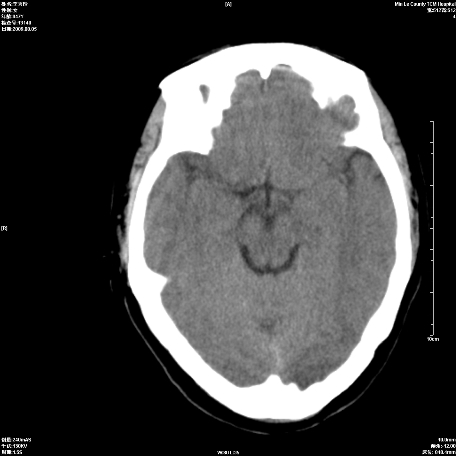

标题: CT21504:女47岁头部外伤一小时,看看右顶叶低密度影考虑什么 [打印本页]

1、女,47岁,头部外伤一小时。

2、右顶叶圆形低密度灶,密度与脑脊液相当,占位效应不明显,周边无水肿带,病灶只占一个层面。

3、考虑脑软化灶,原因?建议增强或mr检查。

密度与脑脊液近似,边界清晰,建议薄层扫描,首考虑蛛网膜囊肿

左顶部蛛网膜囊肿,后枕部头皮血肿。

右侧顶叶类似囊状低密度灶;建议行mri检查。

密度与脑脊液近似,边界清楚,考虑蛛网膜囊肿,建议mri或冠状位扫描